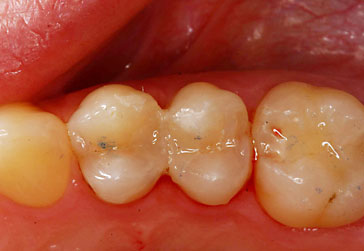

Compositerestauration

![]() |

Kunststoffrestaurationen

Zahnärztliche Kunststofffüllmaterialien eignen sich hervorragend für die substanzschonende Versorgung kleiner bis mittelgroßer Defekte am Zahn. Hinsichtlich Härte, Abriebfestigkeit und Stabilität gegenüber Flüssigkeiten (z.B. Speichel) haben sie bessere mechanische Eigenschaften wie Amalgamfüllungen. Bei ausgedehnten Defekten jedoch stoßen die Kunststofffüllungen an die Grenzen ihrer Dichtigkeit und Stabilität. In solchen Fällen ist, je nach Größe der Defekte, Einlagefüllungen wie Keramikinlays, Goldinlays oder Kronen bzw. Teilkronen den Vorrang zu geben.